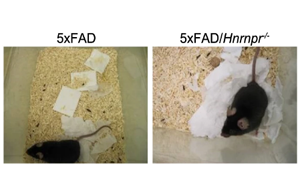

德國維爾茨堡大學醫院(University Hospital Wuerzburg)的Abdolhossein Zare和Saeede Salehi等研究人員開展了一項突破性研究。他們發現RNA結合蛋白hnRNP R能特異性結合tau編碼基因Mapt mRNA的3'非翻譯區(3'UTR),促進其在軸突中的定位和局部翻譯。通過構建hnRNP R基因敲除小鼠與5xFAD AD模型小鼠雜交,研究人員觀察到這些小鼠大腦中磷酸化tau聚集和Aβ斑塊顯著減少。